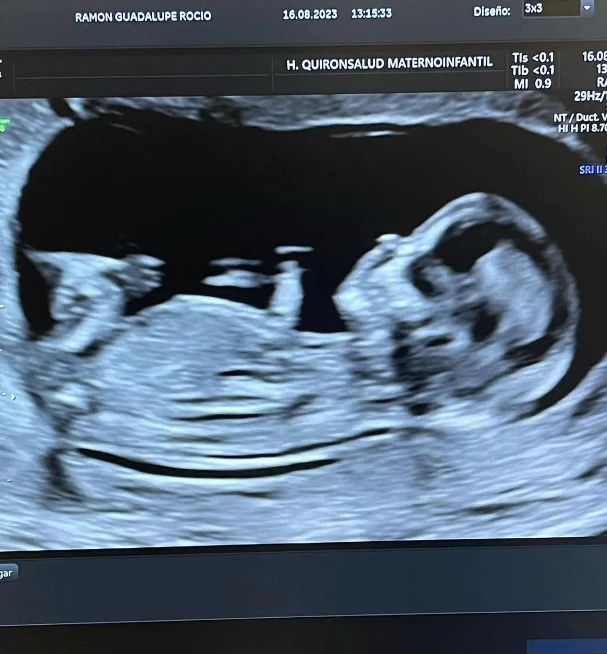

Viviendo un gran momento de su carrera en el Betis de España, mientras se rumorea que su destino podría estar en Inglaterra o algún equipo más top, sorprendieron a propios y extraños. El secreto estaba muy bien guardado junto a Guadalupe 'Wada' Ramón, su novia, y será el primer hijo de la pareja.

“De repente, se frenó el tiempo. Cambió todo... La agenda, los proyectos y las prioridades. Irse hacia adentro ahora es el único camino porque se está gestando nuestro sueño más grande”, comentó la pareja que espera con muchas ansias la llegada de este bebé.